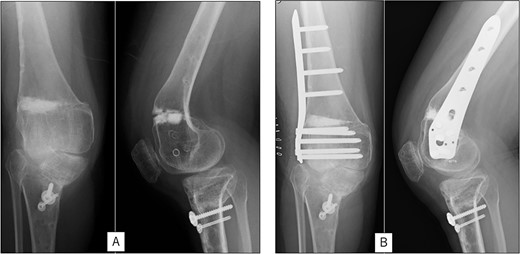

A 23-year-old woman presented with bilateral knee pain and gait abnormalities owing to marked lower extremity deformity. She was diagnosed with EVC as a child but had never been followed up by orthopedics because she was not in pain. On physical examination, marked valgus instability was observed in both knees, and the motion of both knees ranged from 10° to 135°. Radiographic examinations of both knees, including computed tomography, showed valgus deformity, lateral and anterior depression of the proximal lateral tibial plateau, and external rotation deformity of the lower leg. Patellar dislocation was observed in the right knee (Fig. 1). The radiological angles are presented in Table 1. The right knee underwent surgery first, followed by the left 10 months later. Lateral and medial skin incisions were made. Extensive lateral retinacular release, fractional lengthening of the distal lateral hamstring, and Z-lengthening of the iliotibial band were then performed. At this stage, peroneal nerve strain was identified, and decompression of the peroneal nerve was performed. Osteotomy was subsequently performed on the tibia. Closed-wedge varus and derotational osteotomy of the proximal tibia and open-wedge varus osteotomy of the distal femoral varus were performed. In addition, vastus medialis advancement was performed on the right knee, and patellar realignment was achieved in extension (Fig. 2). However, the knee showed a subluxation tendency owing to flexion of >30°; therefore, the postoperative rehabilitation plan progressed more slowly than that of the left knee. Range of motion training began on the left knee immediately after surgery without any restrictions, but on the right knee only after 3 weeks of postoperative immobilization in the extended position. However, ambulation exercise was performed on both knees with no loading for 3 weeks, then partial loading was initiated, and full loading was permitted at 8 weeks postoperatively. Early postoperative standing radiography showed residual mild valgus deformity of the lower limbs (Fig. 2, Table 2). In addition, the right knee showed patellar re-dislocation 2 months postoperatively, and the patellar deformity gradually progressed owing to the femoral implant; therefore, the patient underwent implant removal, tibial tubercle transfer, and medial patellofemoral ligament reconstruction 1.5 years after the initial surgery (Fig. 3). Six months later, she fell while walking and developed a fracture at the osteotomy of the right femur; open reduction and internal fixation were performed (Fig. 4). The remaining years passed uneventfully, and 10 years after the initial surgery, the patient still had mild valgus deformity of the lower limbs, but had no recurrence other than that experienced immediately after surgery, no complaints of knee pain, and a stable gait (Fig. 5, Table 2).

Radiography after right patellar re-dislocation and repair surgery: (A) the patella is eroded owing to contact with the femoral plate. (B) Skyline view after patellar repair surgery. (C) Anteroposterior and lateral view after patellar repair surgery.

Radiography after fracture at the osteotomy of the right femur. (A) anteroposterior and lateral view immediately after fracture. (B) After open reduction and internal fixation.